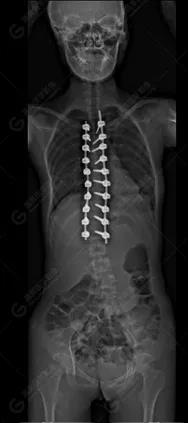

15歲女性,發(fā)現(xiàn)特發(fā)性脊柱側(cè)彎3年,于2019年1月23日來到廣東高尚醫(yī)學(xué)影像診斷中心行EOS檢查,2019年2月行手術(shù)治療后多次到中心行EOS復(fù)查。

2019-02-01

脊柱側(cè)彎最重要一個臨床參數(shù)是側(cè)彎角(Cobb角),目前臨床公認(rèn)的Cobb角>10 °診斷為脊柱側(cè)彎;如Cobb角進(jìn)行性持續(xù)性增加>40 °需要手術(shù)矯正治療。

本例患者胸椎右側(cè)彎,Cobb角(T6/T12)為47°,遂行手術(shù)矯正治療。術(shù)后多次隨訪的Cobb角(T10/L3)為12°-15°之間,較術(shù)前明顯縮小。